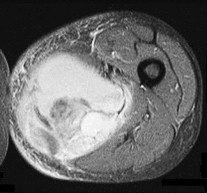

Figures 7a through 7d are the radiograph, MR images, and biopsy specimen of a 35-year-old man who has a painful, slowly enlarging knee mass. Which chromosomal translocation is characteristic of this pathology?

Synovial sarcoma is a soft-tissue sarcoma that usually occurs in young adults. Synovial sarcoma often causes pain, unlike most soft-tissue sarcomas, which generally do not cause pain. Imaging characteristics include soft-tissue calcifications on plain radiographs and a heterogeneous mass that is generally isointense to muscle on T1-weighted images and hyperintense to muscle on T2-weighted images. There are biphasic and monophasic types of synovial sarcoma. The biphasic

type, which is depicted here, has both spindle cell and epithelial components and will stain for both vimentin and cytokeratin. More than 90% of patients with synovial sarcoma have a characteristic genetic translocation of t(X;18), which results in the fusion protein SS18-SSX. This translocation can be stained for use of florescence in situ hybridization technology. t(11;12) is seen in Ewing sarcoma. T(9;22) is seen in extraskeletal myxoid chondrosarcoma. t(12;16) is seen in myxoid liposarcoma.